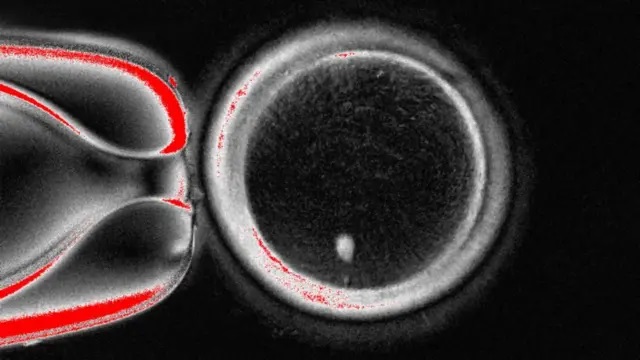

( วงกลมขนาดใหญ่นี้คือไข่ที่ถูกมองผ่านกล้องจุลทรรศน์ จุดสีขาวบริเวณด้านล่างคือสารพันธุกรรมที่ถูกย้ายจากเซลล์ผิวหนังมาใส่ไว้ )

อย่างไรก็ตาม ไข่ดังกล่าวจะยังไม่สามารถผสมกับอสุจิได้ทันที เพราะมันมีโครโมโซมครบชุดอยู่แล้ว

โดยปกติแล้วมนุษย์จะสืบทอดดีเอ็นเอจากพ่อและแม่มาคนละ 23 แท่ง จนรวมกันเป็น 46 แท่ง ซึ่งในไข่ใบนี้มีครบอยู่แล้ว